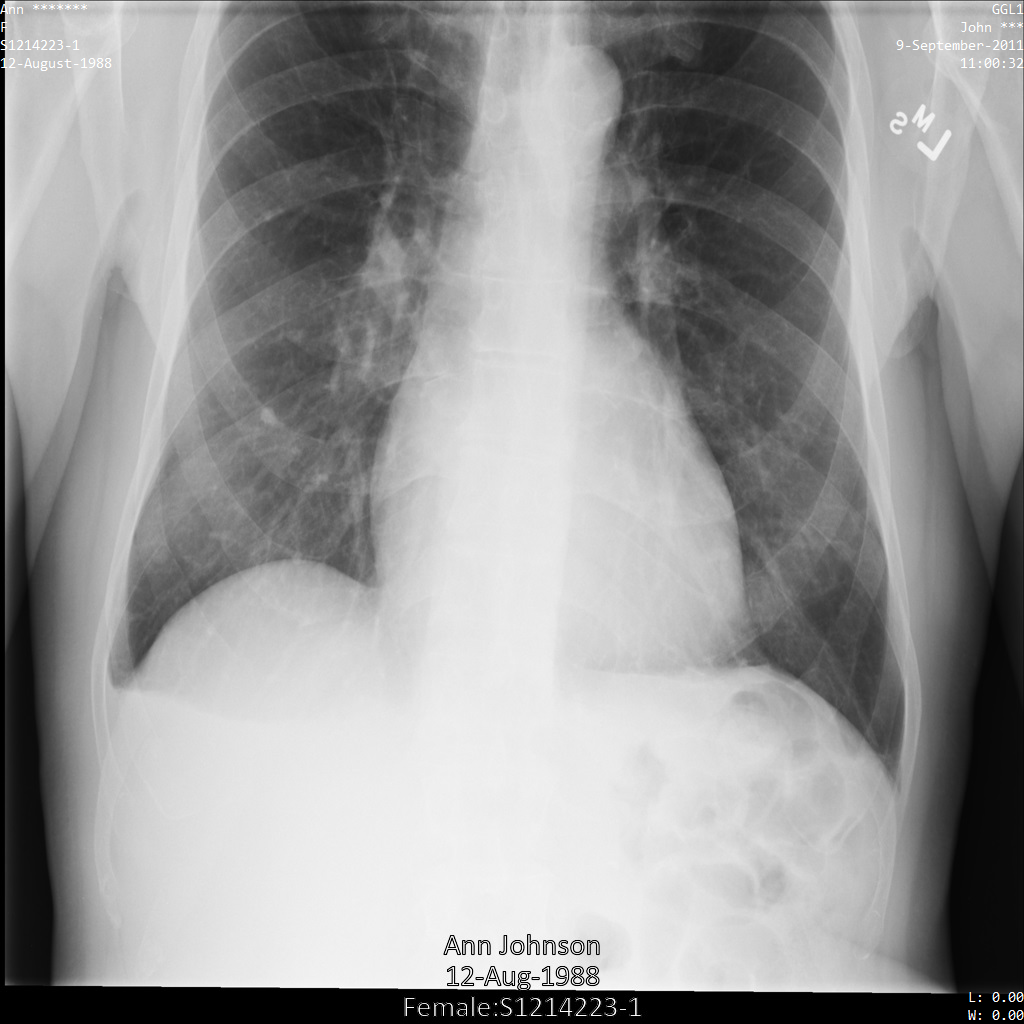

다음 각 섹션에서는 다양한 방법을 사용하여 DICOM 데이터를 익명화하는 방법을 설명합니다. 익명화된 이미지의 출력은 각 샘플에 제공됩니다. 각 샘플은 다음과 같은 원본 이미지를 입력으로 사용합니다.

각 익명화 작업의 출력 이미지를 이 원본 이미지와 비교하여 작업의 효과를 확인할 수 있습니다.

Cloud Healthcare API에 이미지를 제출하면 이미지가 다음과 같이 표시됩니다. 이미지 상단 모서리에 표시되는 메타데이터가 수정되었지만 이미지 하단에 있는 번인 보호 상태 정보(PHI)는 유지됩니다. 번인 텍스트도 삭제하려면 이미지에서 번인 텍스트 수정을 참조하세요.

REST